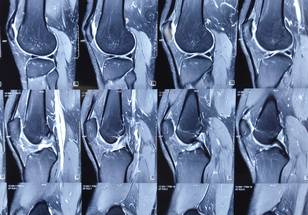

In this case report, researchers Mohamed A. Gouda, Maria A. Zarzour, Ara A. Vaporciyan, Kalevi Kairemo, Hubert H. Chuang, and Vivek Subbiah from The University of Texas MD Anderson Cancer Center and Sarah Cannon Research Institute discuss the case of a patient with a EWSR1-NFATC2 fusion positive bone sarcoma who had exceptional tumor control through using pazopanib and surgery for an overall duration exceeding 5 years. The report also reviews the literature on EWSR1-NFATC2 translocation-associated sarcomas and use of pazopanib in bone sarcomas.